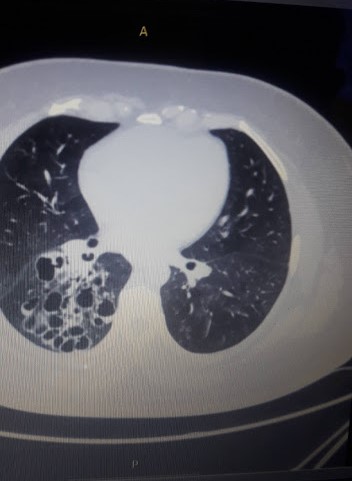

draurtecho Oct 4, 2023 La EPOC y las bronquiectasias comparten síntomas comunes de tos con producción de esputo abundante y purulento; asi como cansancio. La EPOC se diagnostica sobre la base de una obstrucción del flujo aéreo poco reversible y, por tanto, medible por Espirometría. Las bronquiectasias se diagnostican en presencia de dilatación y engrosamiento de la pared de las vías respiratorias, evidenciadas en una TAC Tórax, por lo tanto, es un diagnóstico estructural. Es importante establecer el diagnóstico de la asociación de Bronquiectasias – EPOC, ya que ello deriva en un tratamiento optimo En resumen, las bronquiectasias y la EPOC pueden coexistir como un síndrome de superposición, Ambos puedan cursar con la misma sintomatología, y empeorar la función pulmonar, por lo que se necesita un diagnóstico y manejo eficaz. No Comments InNeumología